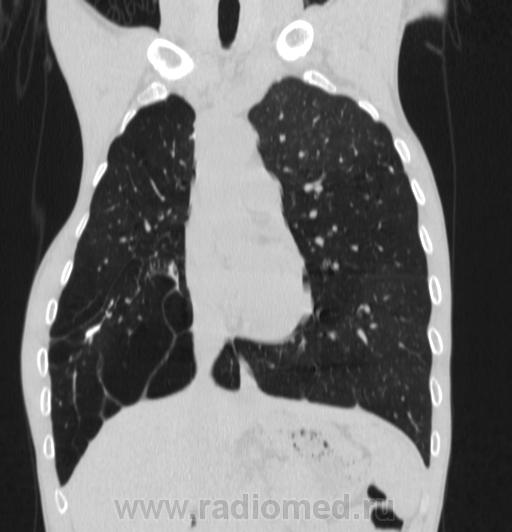

Состояние после торакопластики.

Молодой человек 30 лет, в 04 году выявлен фиброзно-кавернозный ТБ, в течение 12 месяцев лечился в стационаре, прооперирован-5реберная торакопластика справа, через 3 года переведен в 3ГДУ, в 10году снят с ДУ по излечению. Пришел провериться по ухудшению состояния. На КТ легких данных за рецидив ТБ, вроде нет. С " торакопластикой" был единственным пациентом на учете.

Состояние после правосторонней 5-реберной торакопластики по поводу ФКТ.Грубые остаточные изменения:поликистоз,буллезно-дистрофические изменения,плевропневмоцирроз правого легкого..Нет ли  мелкоочаговой диссеминации в обоих легких?Нужен Rархив.(ПТД).

Нет, это кальцинаты и более плотные уже. Архив только пленочный, 8 лет назад "цифры" не было. Можно и пленку перефотать...

Редко встречалось, а на КТ вижу впервые, спасибо за случай! На показанных изображениях отсевов не увидела.